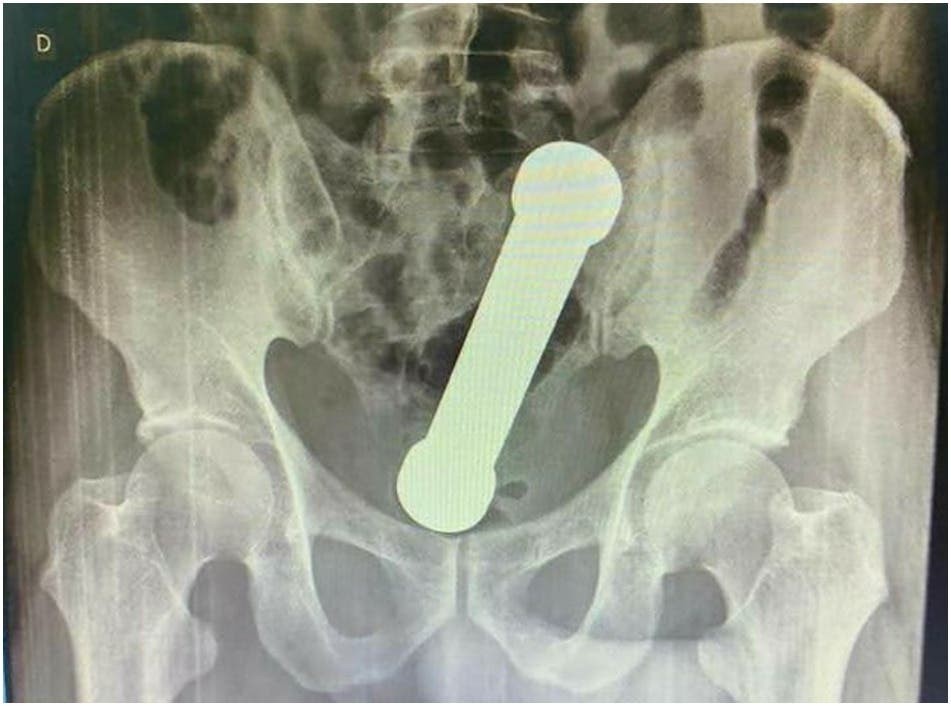

Las radiografías abdominales revelaron que el hombre tenía una mancuerna de 20 centímetros atorada a la altura del lugar en que el colon se conecta con el recto.